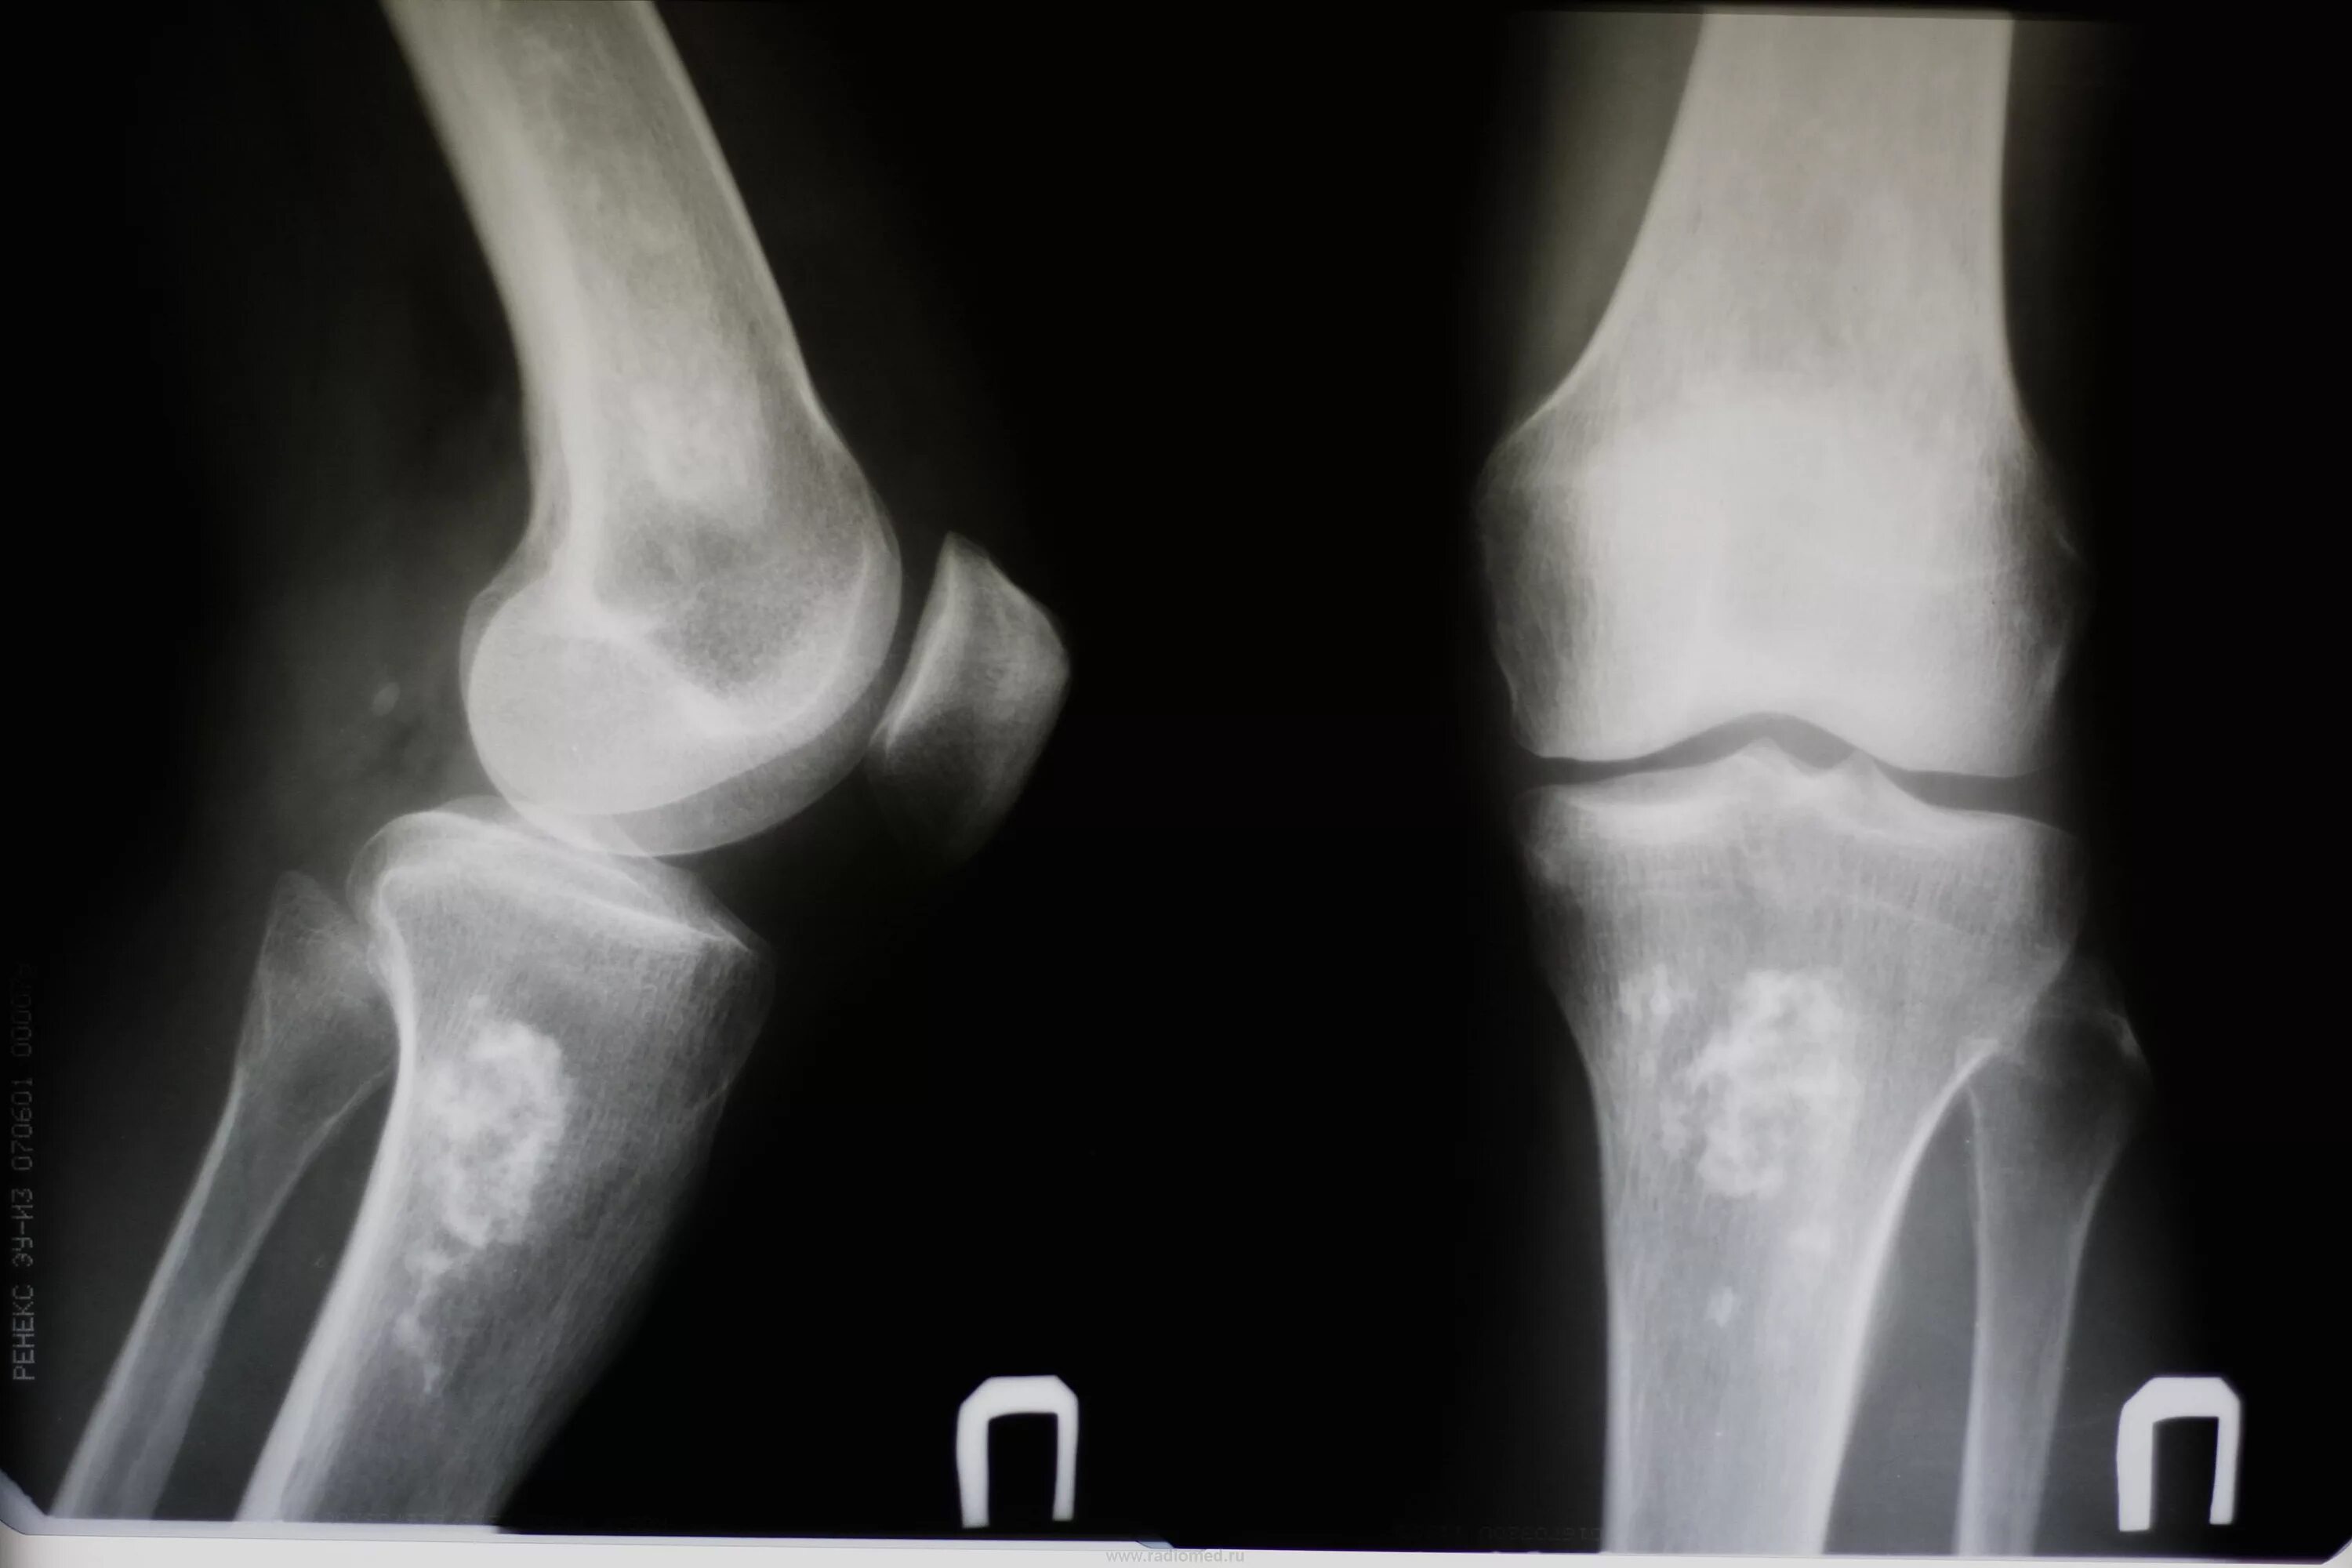

Рентгенография коленного сустава 2 проекции